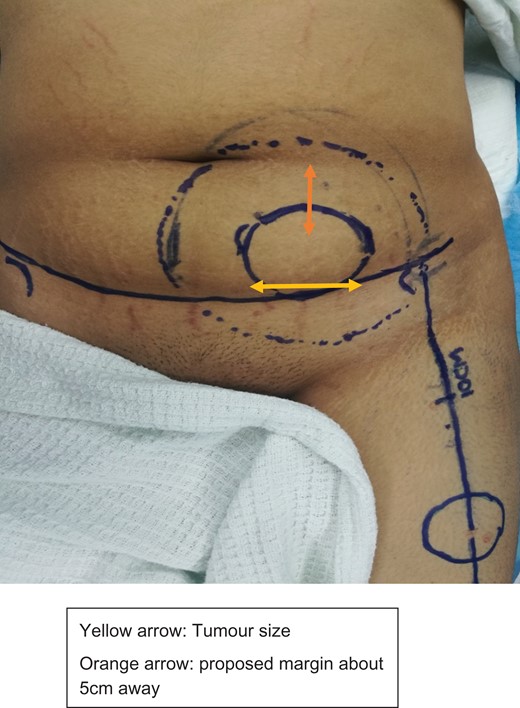

Intraoperatively, lower abdominal incision made, abdominal flap raised up till supraumbilical level, depth until suprafascial layer. Tumour located at left iliac fossa region, well circumscribed, size ~6 × 4 cm2. Tumour was excised with 5 cm margin together with underlying peritoneum. It left ~25 × 20 cm2 defect over anterior abdominal wall, exposing the omentum and bowels (Figs 2–4).

Marking of incision abdominal flap, tumour with 5 cm margin, and donor flap.

Tumour was excised with 5 cm margin together with underlying peritoneum. It left ~25 × 20 cm2 defect over anterior abdominal wall, exposing the omentum and bowels.